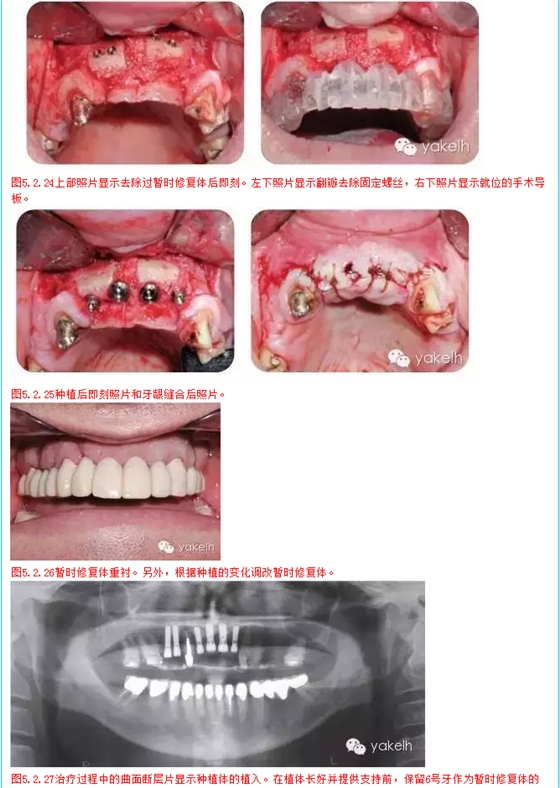

上頜天然牙牙支持式固定橋更換為種植體支持式固定橋,其他用單冠及牙支持式固定橋修復(fù)(病例)

¤¤因關(guān)鍵基牙遠(yuǎn)期預(yù)后較差,臨床上經(jīng)常需要將牙支持式固定橋換成種植體支持式固定橋。治療的困難在于整個治療過程中因為患者不能接受活動的暫時修復(fù)體,需要制作固定的暫時修復(fù)體。該患者在其他國家進(jìn)行了整個牙合重建。但對結(jié)果不滿意,也不喜歡美學(xué)效果,上唇過于凹陷,咬合也不舒適。此外,修復(fù)體結(jié)構(gòu)和邊緣適合也不足,需要全部更換。部分牙齒缺失,并且關(guān)鍵基牙—右上尖牙,遠(yuǎn)期預(yù)后差。因此,治療計劃包括植骨在內(nèi)的口腔種植手術(shù)。

4,5,7,8,9,10號牙齒種植修復(fù),6號牙由種植固定橋修復(fù)

其他缺牙采用牙支持式固定橋修復(fù)

治療步驟概要

復(fù)診 完成治療

1 在2天內(nèi)分2次全牙列暫時性修復(fù)

2 種植區(qū)口腔外科骨移植手術(shù)

3 調(diào)整和修改暫時修復(fù)體

4 牙髓治療和牙髓再治療

5 完成下頜牙治療

6 4,5,7,8,9,10號牙種植修復(fù),6號牙仍作為暫時修復(fù)體的基牙

7 待種植后愈合和骨整合,調(diào)整和維護(hù)暫時修復(fù)體

8 安置種植體基臺,拔除6號牙,制作種植體支持式暫時修復(fù)體

9 拔牙創(chuàng)愈合

10 最終的上頜修復(fù)體,2,3號牙為單獨修復(fù),4號至10號牙為種植固定橋,6號牙為橋體,11號至15號牙為牙支持式固定橋